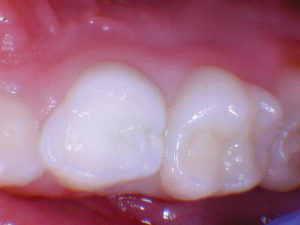

Un nuevo paciente de 7 años presentó una importante descomposición e hipocalcificación en el primer molar permanente superior derecho. Durante mucho tiempo se ha demostrado que los primeros molares permanentes cariados e hipocalcificados en pacientes pediátricos le dan al profesional un dilema restaurador difícil. ¿Deberíamos intentar prepararnos y restaurarlos conservadoramente? ¿Deberíamos ser más agresivos y restaurar con una cobertura completa como una corona de acero inoxidable bien adaptada? Activa proporciona una gran alternativa en estos casos, con liberación de calcio, fosfato y fluoruro junto con alta resistencia y resistencia a la fractura.

Figura 2. Una vez que se excavó la descomposición y se colocaron los márgenes en superficies sólidas, se colocó un bisel pesado en el esmalte para aumentar la resistencia de la unión y la integridad marginal. El área oscura central era sólida. El diente estaba revestido con una base / revestimiento Activa. |

Figura 4. El seguimiento de 18 meses no mostró fracturas y márgenes intactos. |